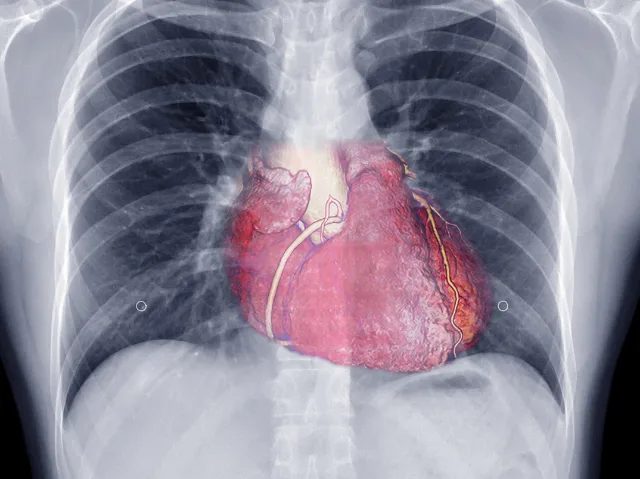

Chest pain is a symptom that can have many potential causes — some benign and others requiring immediate medical attention. Causes may include:

• Heart attack or ischemia

• Angina (reduced blood flow to the heart)

• Pericarditis (inflammation of the heart lining)

• Acid reflux or GERD

• Pulmonary conditions (e.g., pneumonia, PE)

• Musculoskeletal pain

Because some causes of chest pain can be life-threatening, prompt evaluation and diagnosis are critical. Early care can save lives and prevent complications.

4. What tests are used to evaluate chest pain?

Diagnostic tests may include an ECG (electrocardiogram), blood tests, stress testing, echocardiogram, or imaging studies. The specific tests depend on your symptoms and risk factors.

5. What are common causes of chest pain?

Common causes include coronary artery disease, angina, acid reflux (GERD), pulmonary conditions, anxiety, and musculoskeletal pain. A thorough evaluation helps identify the exact cause.